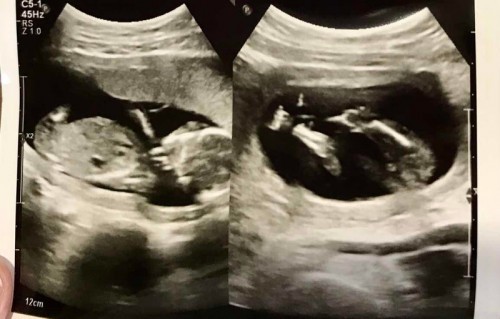

7 เดือนแล้วยังเห็นไม่ชัดเลยค่ะ

16week แล้วค่ะแต่ยังไม่รู้เพศเลย😊

รออีกนิดน้าเเม่ อายุครรภ์เยอะๆชัวร์กว่าค่ะ เเต่ของบ้านนี้หมอบอก ลูกสาว เลยไม่รู้คนอื่นลูกสาวได้เเบบไหน นี่ก็ยังต้องลุ้นต่อค่ะ

กำลังตั้งครรภ์